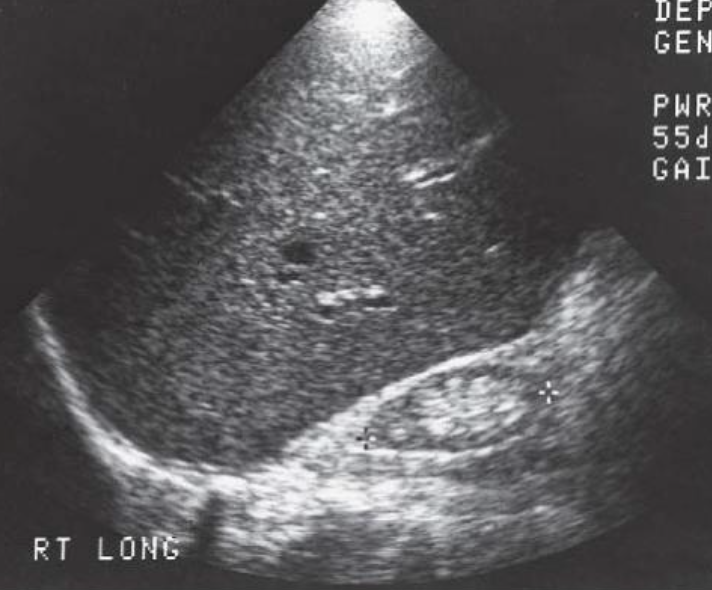

Nephroblastoma (Wilm’s Tumor) → 2nd most common peds abdominal cancer

clinical hx: 2-5 years, unilateral, Beckwidth-Wiedmann

s/sx: abdominal swelling, abdominal pain

2D US: vascular involvement, large solid mass, distorts renal cortex, sinus, pyramids and contour, hydronephrosis, extension into renal vein, IVC, contralateral kidney, homogenous to complex, calcifications, well-defined

color doppler: hypovascular/vascular

DDX: neuroblastoma, hepatoblastoma